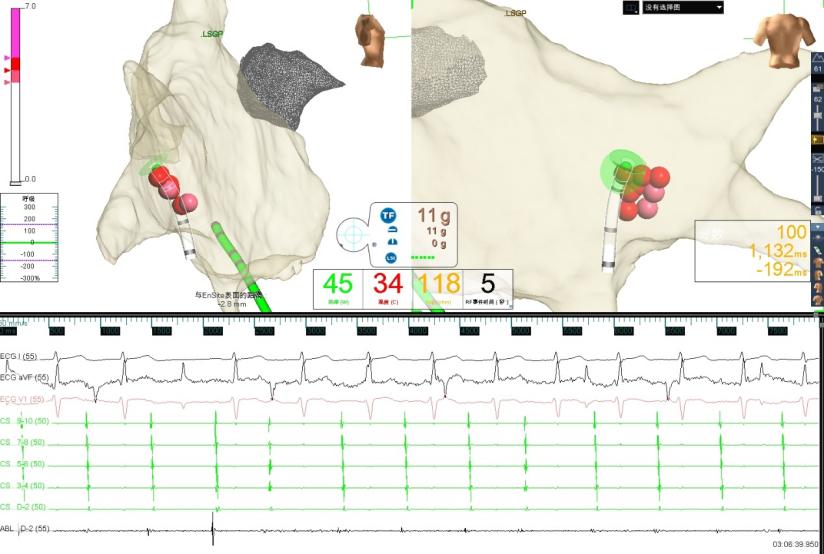

经与患方充分沟通治疗方案后,5月9日,在寿锡凌教授指导下,酉鹏华副主任医师、韩稳琦博士、赵永勇主治医师等为患者局麻下成功行经导管心脏迷走神经节消融改良术。术中先行心脏腔内电生理检查术,消融前测窦房结恢复时间(SNRT):1404ms,房室结文氏点(CSNRT):700ms,依次消融左房左上神经节丛(LSGP)、左房左下神经节丛(LIGP)、左肺静脉间神经节丛(MTGP)、左房右前神经节丛(RAGP)、左房右下神经节丛(RIGP),消融RAGP时窦性心房频率从40-46次/分提升至95-100次/分,但表现为房室传导阻滞,房室非1:1传导特点,心室率提升不明显,消融RIGP时房室结迷走张力减低,房室传导明显改善,房室呈1:1传导,心室频率提升至95-100次/分。

图2 消融右前GP时窦性心房频率增快,房室非1:1下传,心室率稍增快

图3 消融右下GP时房室传导恢复为1:1下传且心室率明显增快

图4 GP消融靶点